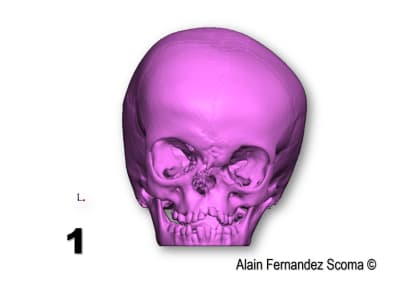

Tien un exemple d'une commande par un Professeur en maxillo- qui me demande : " Alain, tu peux étudier comment segmenter ce massif facial (1) pour reconstruire une forme correcte (2)". Le jour de chirurgie (3) ils sont utilisé un guide de coupe (4)pour tracer les segments et découper la calotte crânienne (5)l'arcade orbitaire... et réorganiser (6) les tronçons. Le scan de contrôle (7) superposé sur l'étude (8) montrent la pertinence du partage. Il y a une découpe dont le tracé à était modifié par rapport à l'étude ce qui m'a fait plaisir de voir justesse d'analyse du chirurgien.